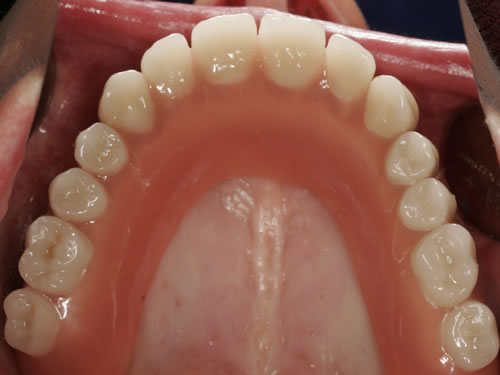

3.4 Reduzierte Bezahnung

Wenn viele Zähne fehlen und nur noch einige erhaltungswürdige Zähne vorhanden sind, die in den neuen Zahnersatz mit einbezogen werden können, dann spricht man von einer reduzierten Bezahnung. Die prothetische Versorgung wird als Hybridkonstruktion bezeichnet, da sie sowohl auf natürlichen Zähnen als auch auf Implantaten befestigt wird. Die Versorgung kann sowohl festsitzend - verschraubt oder zementiert - gestaltet werden (Abb. 3.24, 3.25), aber auch herausnehmbar, wobei dann häufig teleskopierende Konzepte verwendet werden (Abb. 3.26, 3.27).

Abb. 3.24: Festsitzende Hybridbrücke auf 4 Zähnen und 6 Implantaten.

Abb. 3.25: Brücken vor der Eingliederung.

Abb. 3.26: Hybridversorgung einer reduzierten Oberkieferbezahnung auf 4 Zähnen und 3 Implantaten.

Abb. 3.27: Ansicht des gaumenfreien, herausnehmbaren Zahnersatzes.